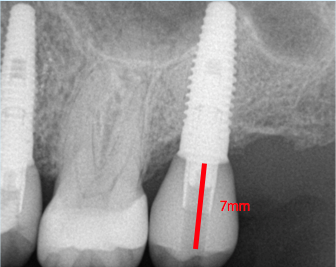

Fig. 1. Occlusal table to platform.

Figure 1